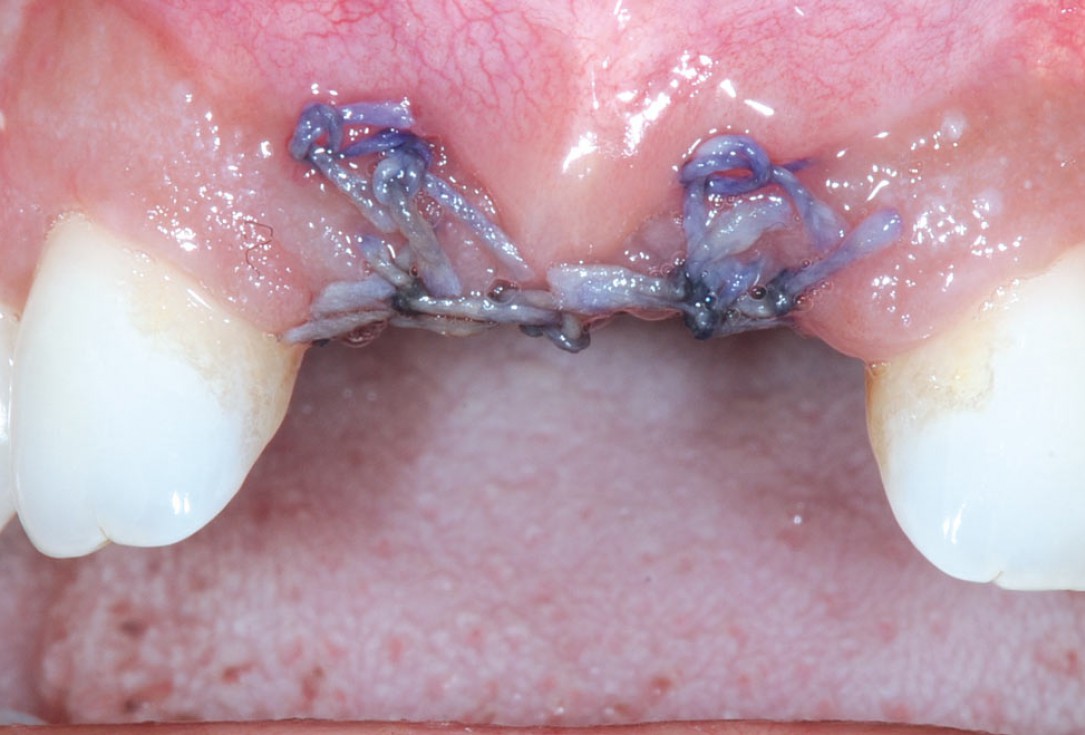

19/26 - 3 weeks post-op: eventless healingBone augmentation in aesthetic zone with maxgraft® bonering - Dr. A. Patel

20/26 - 6 weeks post-op: sutures were removedBone augmentation in aesthetic zone with maxgraft® bonering - Dr. A. Patel